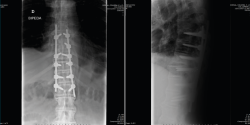

Se puede observar con más claridad la lesión traumática T10/T11 y la sindesmofitosis de todo el raquis en el corte sagital de una tomografía axial computarizada de cuerpo (body TAC) (Figura 2).

Figura 2. Corte sagital de tomografía axial computarizada dorsolumbar.